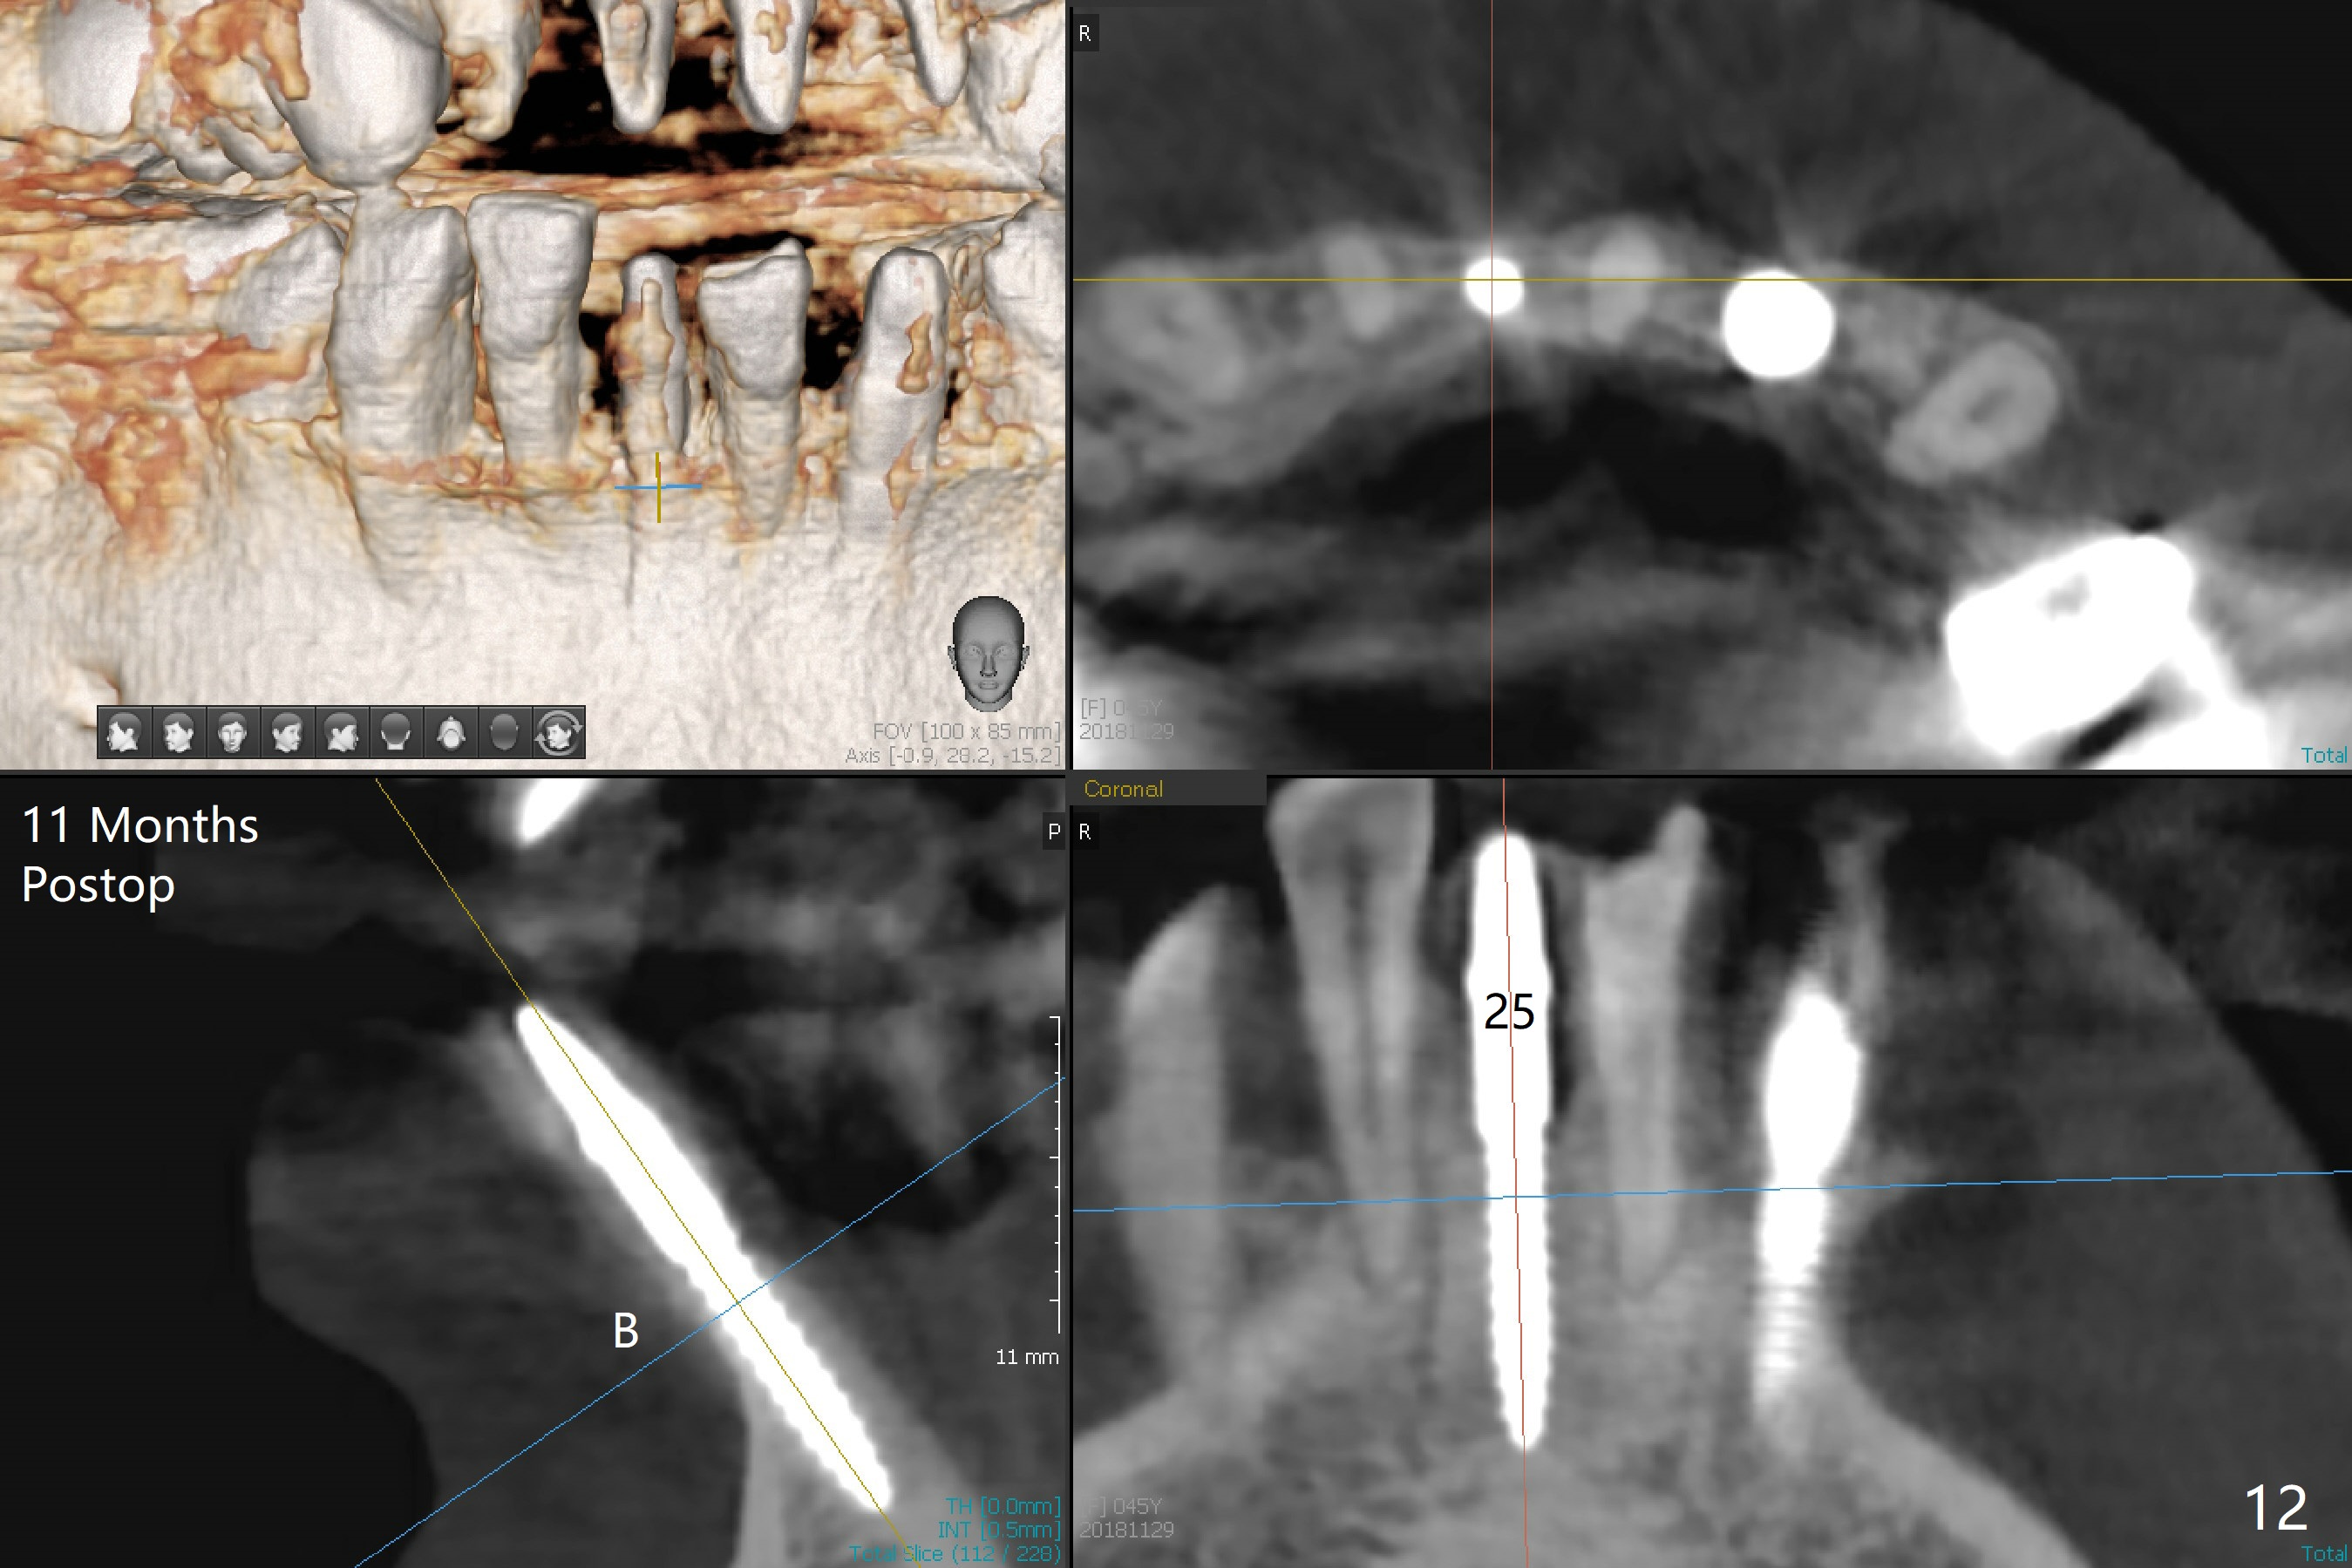

There is gingival inflammation at #25 buccally (Fig.1) and lingually (Fig.2). The bone loss is severe (Fig.3). Soft and hard tissue heights are 5 mm (cuff will be 4 mm) and 10 mm (implant will be 12 mm with 2 mm outside the native bone, Fig.4). The apex of the affected tooth appears deviated distal (Fig.5 *). The initial osteotomy happens to follow the long axis of the socket (Fig.6); to establish a correct trajectory, a new osteotomy should be made at the site labeled as a red line. In fact it is executed as planned (Fig.7). Because of the narrow flat ridge buccolingually, a 2.5x12(4) mm 1-piece implant is placed with >40 Ncm (Fig.8). With deeper placement of the implant, Vanilla graft is placed in 2 steps (Fig.9,10). The patient will return 2.5 months for extraction and implant of the fused teeth #22 and 23. No implant threads are exposed 10 months postop (Fig.11). CT taken 11 months postop shows that the 2.5 mm implant is in the middle of the bone (Fig.12) or 2 years post cementation (Fig.13).